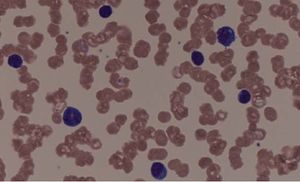

혈액 도말은 혈액 질환 진단을 위해 혈액을 얇게 펴서 슬라이드에 고정, 염색하여 현미경으로 관찰하는 검사법이다. 혈액 도말 검사 과정은 혈액을 슬라이드에 얇게 펴 바르고, 메탄올로 고정, 염색하는 순서로 진행되며, 염색 후에는 현미경으로 관찰하여 백혈구, 적혈구, 혈소판의 형태와 수적 이상을 확인한다. 이 검사를 통해 빈혈, 백혈병, 감염성 질환 등 다양한 질병을 진단하며, 말라리아와 같은 기생충 감염 진단에도 활용된다.

염색 후 단층을 최대 1000배 배율로 현미경으로 관찰하며, 개별 세포를 검사하고 형태를 기록한다.[1][2] 최근에는 자동 혈구 계산 장치를 먼저 사용하고, 기계 산정에서 이상이 있거나 혈액 질환이 있는 환자의 경우 혈액 도말 검사를 추가로 시행한다.[42][64]

현미경을 통해 혈액 세포의 형태, 크기, 수, 염색성 등을 관찰하여 이상 유무를 판단한다. 정맥 등에서 채취한 말초 혈액[12]을 슬라이드 글라스 위에 얇게 펴서(도말) 건조시킨 후 염색하여 관찰한다.

혈액 도말 검사를 통해 적혈구의 모양, 크기, 착색을 현미경으로 검사하는 것은 빈혈의 원인을 파악하는 데 유용하다. 철 결핍성 빈혈, 겸상 적혈구 빈혈, 거대 적아구 빈혈, 미세혈관병성 용혈성 빈혈과 같은 질환은 혈액 도말에서 특징적인 이상 소견을 보인다.[2] 정상 적혈구는 직경 7-8 μm이며, 원형이고 중앙이 밝게 보인다(중앙 담명).